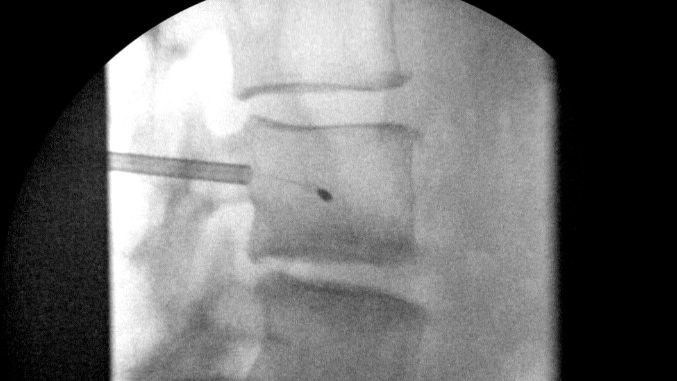

Doug Beall going over the top of screw

image_d763a6f2-305e-4d46-948b-68926a28257620220714_162000.jpg

image_b1888c74-3b51-4a67-af3a-4fc0d9216f5a20220714_161956.jpg

image_5c396b3d-57d1-4a7d-8f47-79217506a40e20220714_161954.jpg

image_c8082d3b-519b-4414-a67e-0560bf23415e20220714_161949.jpg